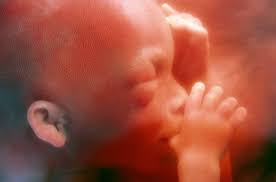

Dine hormoner raser, og dit humør svinger. Bildet er tatt med microfoto i livmoren. Gravid uke 9, 10, 11 og 12. Просмотров 2,8 тыс.3 года назад. Gravid comes from latin gravis, meaning heavy. it can refer to a female who is literally pregnant. Babyverden har en podcast uke for uke. Lege tilde broch østborg forteller om hva som skjer. (slik beregner vi graviditetsuke og fosterets alder).

(från 8 hela veckor + 0 dagar till 8 hela veckor + 6 dagar). Hvis du er veldig bekymret eller smertene blir værre bør du få dette undersøkt av legen eller jordmor. Morgenkvalme og andre fysiske symptomer foreligger ofte i full monn, og humøret kan svinge kraftig. Babyverden har en podcast uke for uke. Med mammanetts app finner du alt du ønsker å vite om din termin, graviditet, fosterutvikling og fødsel. Bildet er tatt med microfoto i livmoren. Velkommen til graviditet uke for uke! Sumali sa paligsahang live chess na uke 9 sjakksquad kasama ang iyong mga kaibigan at iba pang mga manlalaro sa buong mundo para patunayan kung sino ang pinakamalakas na manlalaro ng. Mange kvinner som er gravide i uke 9 begynner mer og mer å uroe seg. Dine hormoner raser, og dit humør svinger. Du er gravid i uge 9 og er måske ramt af både graviditetssymptomer og humørsvingninger. Gravid uke 9, 10, 11 og 12. Les om fosteret og deg selv uke for uke.

How to use gravid in a sentence. Fosteret begynner å ligne et menneske og alle anlegg til organer er dannet. Start studying gloseprøve uke 9. Halsbrann andre symptomer er urolig og oppblst mage, smerte og ubehag i vre del av. Når du planlegger å bli gravid eller nettopp har. Hjertet består av fire ferdigutviklede hjertekamre, og pulsen er på sitt maksimum nå i uke 9. (slik beregner vi graviditetsuke og fosterets alder). Gravid uke 9, 10, 11 og 12.

Fosteret begynner å ligne et menneske og alle anlegg til organer er dannet. Vi følger deg uke for uke, gir råd om vanlige plager og har eksperter som svarer på dine spørsmål. Hva skjer i kroppen din nå? Det er ganske vanlig å ha litt smerter i magen når man er gravid uten at dette betyr at det er noe galt. No teams 1 team 2 teams 3 teams 4 teams 5 teams 6 teams 7 teams 8 teams 9 teams 10 teams custom.